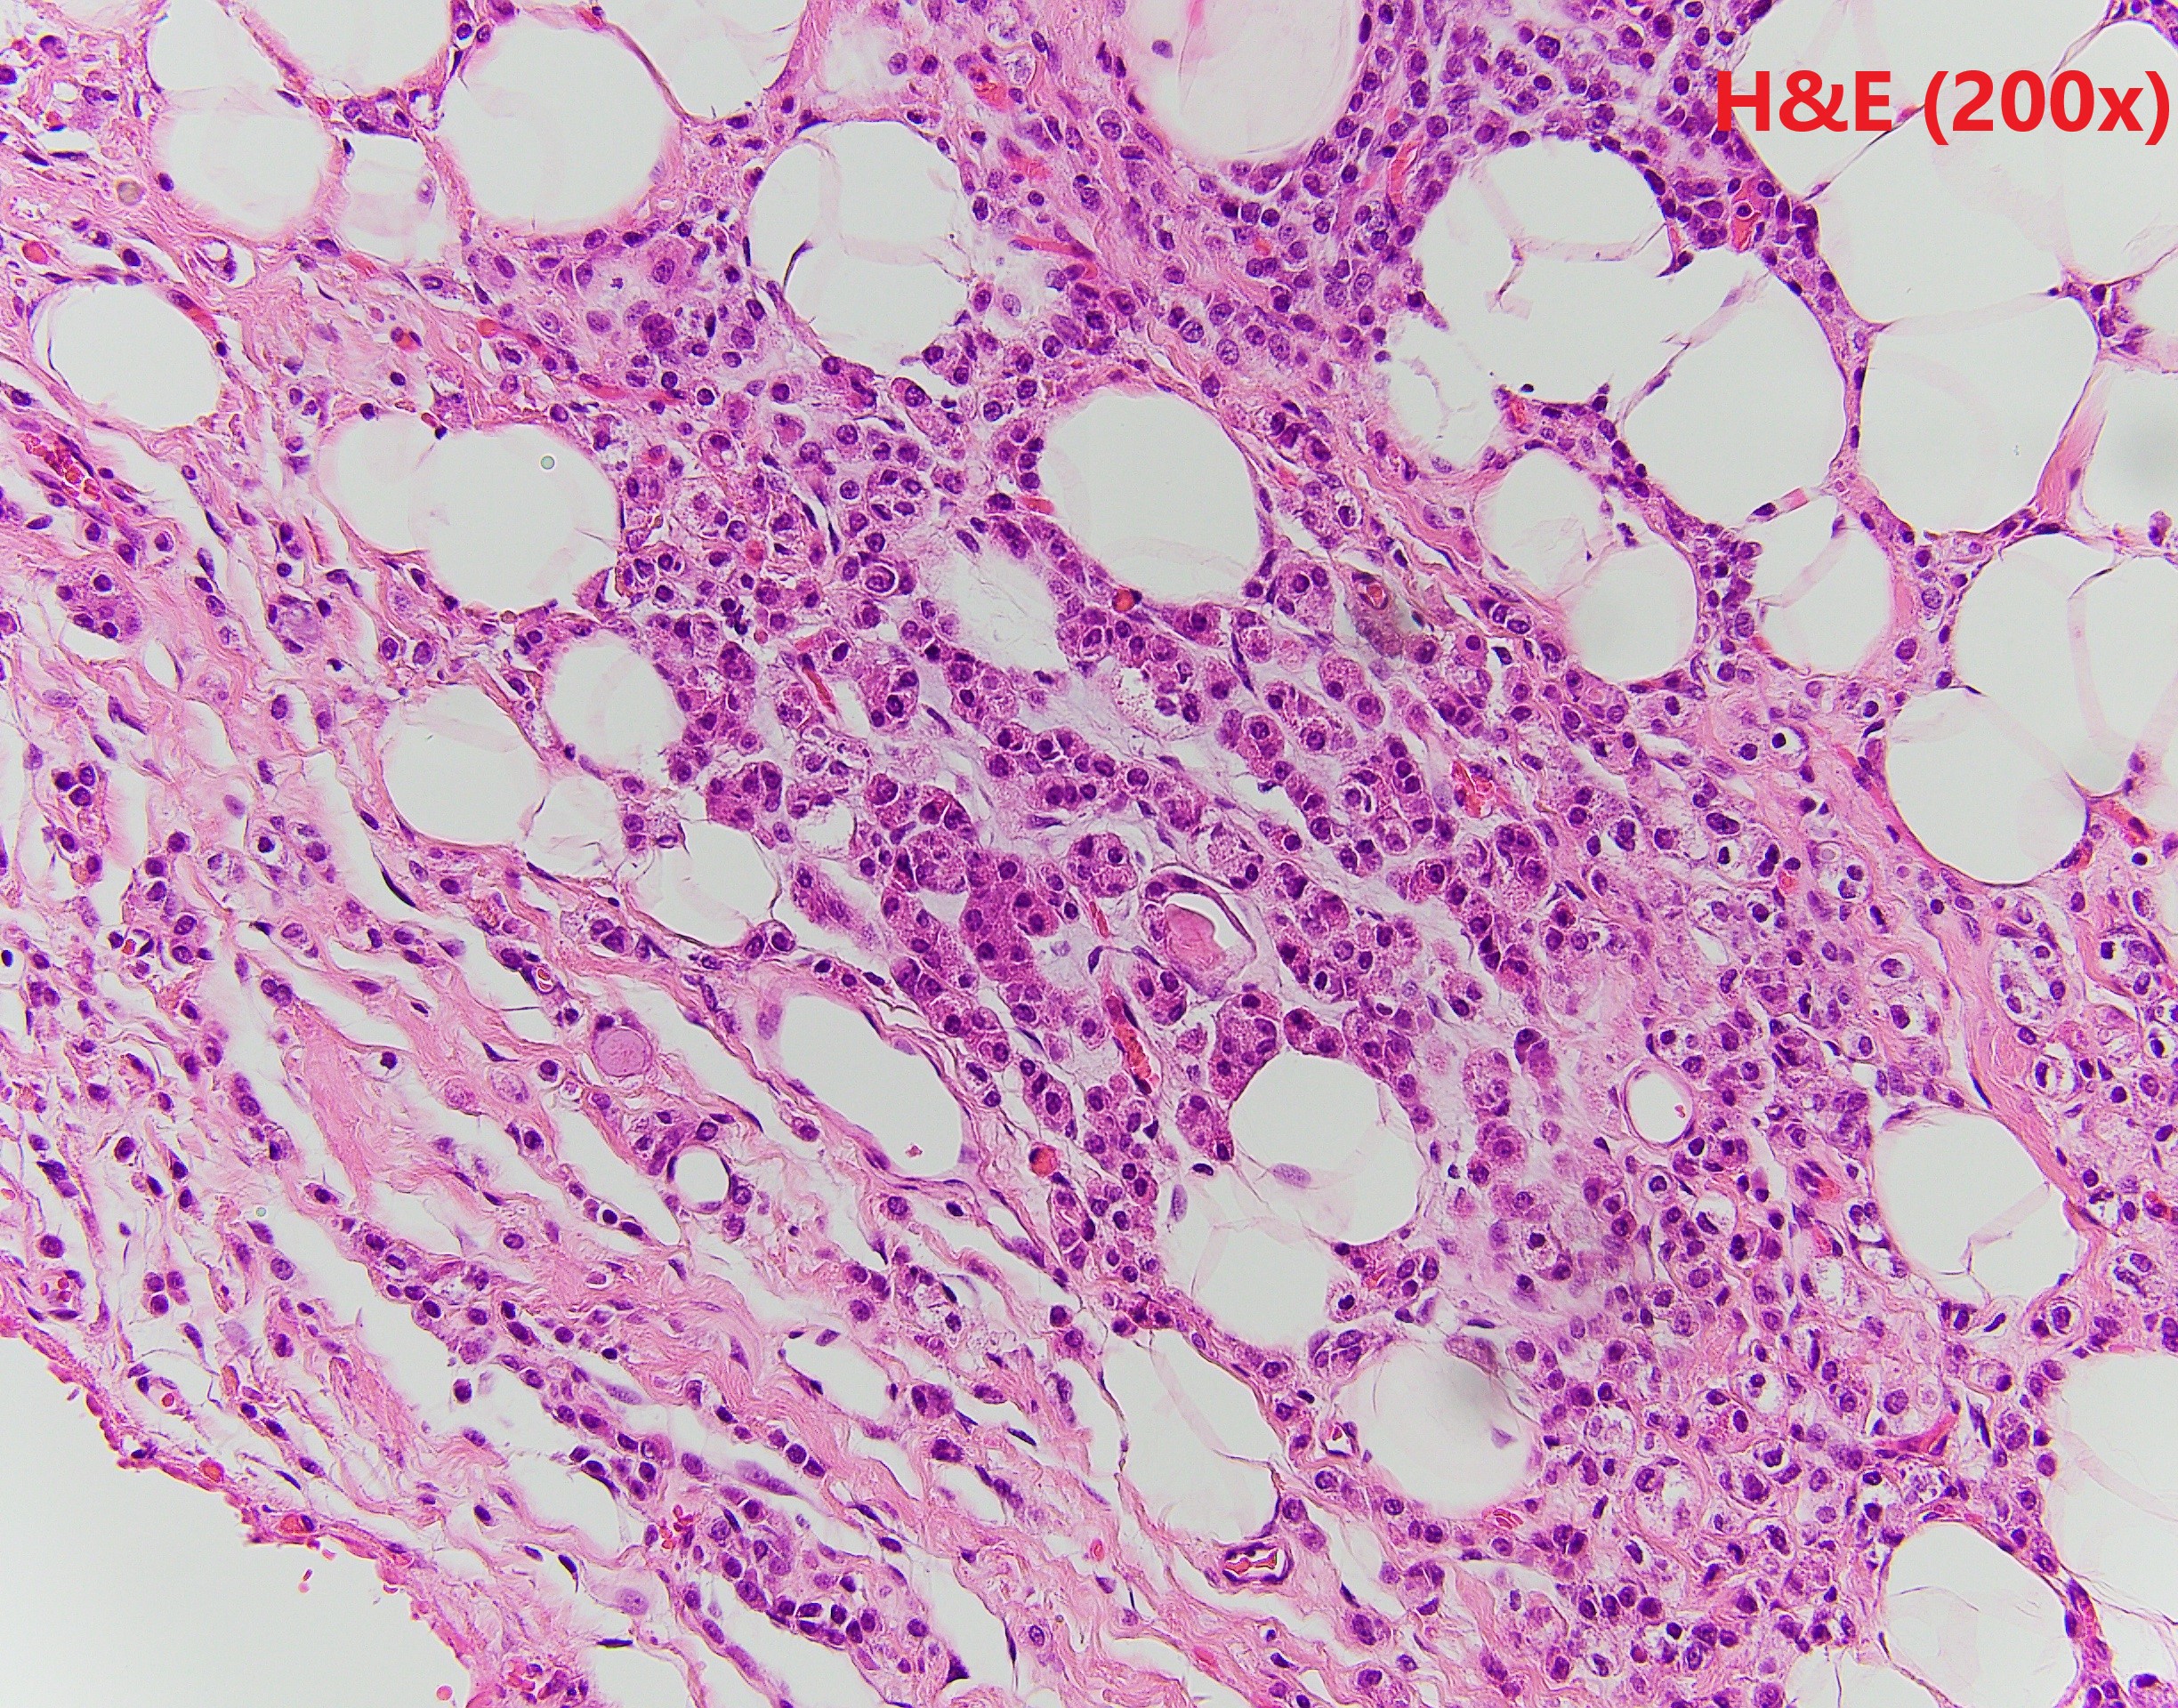

The patient is a middle-aged female with an irregular enhancing mass in the right breast. After resection, IHC revealed GATA3 and CK7 positivity and p63 negativity. Further studies of lysozyme and a1-antichymotrypsin are shown.

Breast acinic cell carcinoma (ACC) is a rare entity and usually affects women aged 20-80 years. Architectural patterns of ACC are variable, ranging from microglandular proliferation to solid. Diagnosis of ACC is mainly based on cytological features. The tumor cells show abundant eosinophilic to clear cytoplasm with coarse granules. The nuclei are usually centrally located with prominent nucleoli. Cytological atypia and mitosis can be seen. The tumor cells are usually triple negative, and positive for S100, EMA, lysozyme and α1-antichymotrypsin. The differential diagnosis is broad depends on cytomorphology. The prognosis of ACC is still unclear because the limited number of cases reported. Most of the reported patient had chemoradiation and surgery.